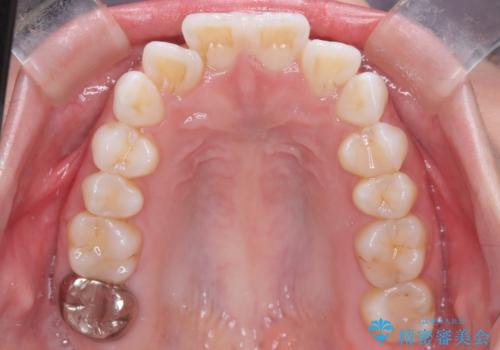

- 前歯が前方に突き出していることによる口元の突出感を改善したいという主訴でご来院されました。

精密検査の結果、歯を後方へ下げるためのスペースが不足していたため、上下左右の4番目の歯(第一小臼歯)を計4本抜歯する計画を立案しました。抜歯によってできたスペースを最大限に活用し、前歯を後ろに下げることで、口元のボリュームを抑え、バランスの良いEライン(横顔のライン)を目指すこととしました。装置は、日常生活で目立ちにくい審美ワイヤーを選択しました。